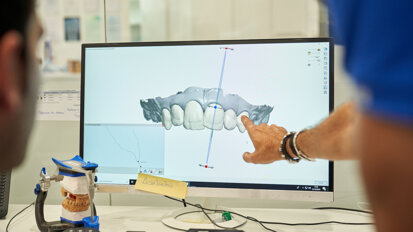

Docięty łącznik na modelu z maską dziąsłową laboratorium przekazało do gabinetu, gdzie następnie na modelu uzupełniłem żywicą przestrzeń pomiędzy łącznikiem a maską dziąsłową (Ryc. 22). Następnie przykręciłem łącznik wg klucza protetycznego w ustach pacjentki i nałożyłem na niego wcześniej przygotowany pierścień z żywicy podpierający dziąsło (Ryc. 23) i doszlifowałem go wiertłami wg standardów preparacji pod korony pełnoceramiczne (Ryc. 24-27). W pracowni pierścień ten został zeskanowany i wg niego zaprojektowano czapkę cyrkonową pod koronę ceramiczną (Ryc. 28 i 29).

Profil ukształtowany przez koronę tymczasową zespoloną z łącznikiem tymczasowym został tym samym precyzyjnie odtworzony w pracy ostatecznej. Taki protokół postępowania był możliwy dzięki pracy w systemie CAD/CAM. Dlatego po zacementowaniu korony na implancie wygląd dziąsła przy nim był bardzo zbliżony do kształtu dziąsła przy zębie jednoimiennym. Różnica w kolorze, która pozostała spowodowana jest niestety, trwałym tatuażem po zaaplikowaniu amalgamatu przed laty.